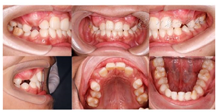

患者身材矮小,肩膀窄而下垂,活动范围大,可在胸前相互靠拢,面中部发育不足;口内检查11部分萌出;31反

。CBCT示11牙根向远中明显弯曲,牙根发育至Nolla9期;21牙根发育至Nolla9期,腭侧见两颗正置锥形多生牙,牙根未发育完成;12、22牙根发育至Nolla9期;23牙冠近中倾斜至62根方。

口内检查:全口口腔卫生较差。11、12、22、42未见萌出。

21部分萌出3~4 mm,牙龈缘稍红肿,与31反

,反覆

1~2 mm,反覆盖2 mm。

26、36釉质表面呈黄褐色,质硬、光滑,探及深窝沟,未探及龋坏。

55、16、65、46探及龋坏达牙本质中层,质软,无松动,叩诊(-),根尖区黏膜未见红肿、窦道等异常,扪诊无不适。

根尖片示:11自根中向远中弯曲约35°,属Ⅱ类弯曲牙,牙根发育至Nolla9期,21牙根发育至Nolla9期,腭侧见两颗正置锥形多生牙;12、22牙根发育至Nolla9期。

CBCT示:上颌恒牙胚萌出间隙不足,根据Moyers混合牙列分析法,牙弓现有长度为177.4 mm,牙弓应用长度为181.6 mm,拥挤度为4.2 mm。42缺失;11、21、22发育至Nolla9期;55、16、65、46冠部低密度影及牙本质中层,根管内未见高密度充填影,根尖周未见明显异常。53、63牙根吸收不足1/3,13、23发育至Nolla8期。